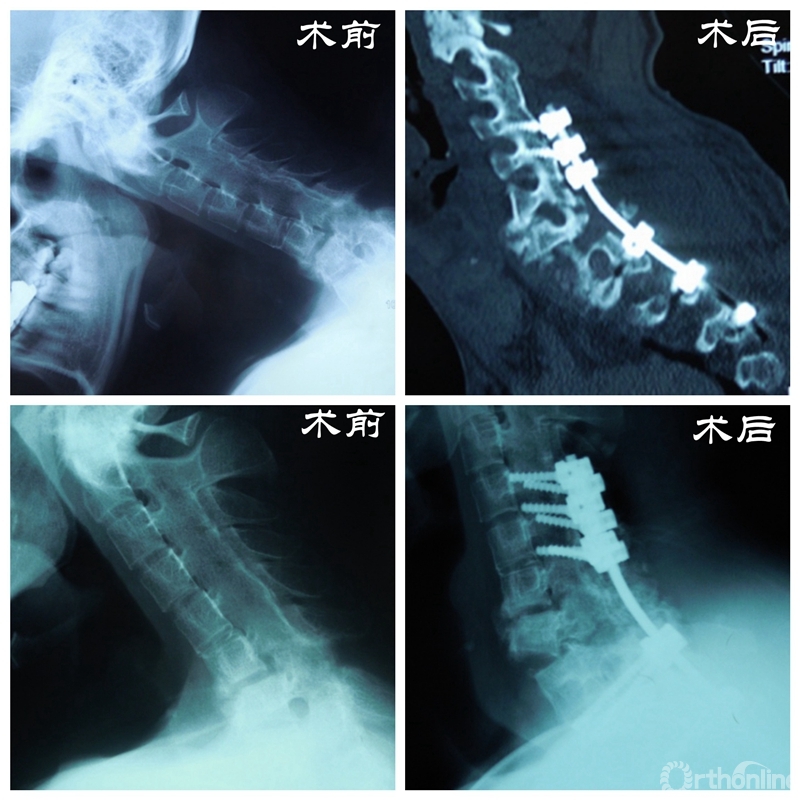

2014年初,丁文元教授像往常一样来到门诊,等在诊室门口的一个小伙子吸引了他的注意。这个小伙子由母亲带着前来就诊,身材高大壮实,但始终不曾抬起头来。经过周密的检查和问诊,丁文元教授得知这个小伙子28岁,名叫大帅(化名),患有强制性脊柱炎颈胸段鹅状畸形,此时也明白了他始终不抬头的原因。

患者资料

门诊结束后,丁文元教授立刻带领团队成员开始查阅大量相关文献,为大帅的手术进行充足的准备和周密的计划。幸运的是手术很顺利,术后复查各项指标恢复良好,大帅的头也抬起了来了,脸上洋溢着久违的笑容,这给了医生和患者家庭极大的信心。

手术步骤